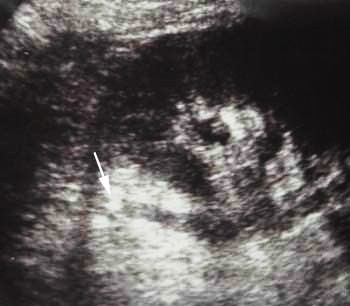

А вот "расширение мочеточника с

видимой причиной для уростаза", гидронефроз

- ren.jpg (32.42 КБ) 5651 просмотр

Все верно.